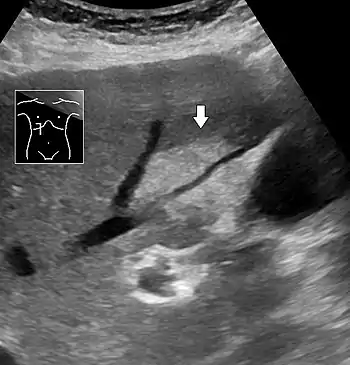

On abdominal ultrasonography, steatosis is seen as a hyperechoic liver as compared to the normal kidney.

- Abdominal ultrasonography with the liver and kidney side by side (left image) may give a false impression of hyperechogenic liver, so it's preferably done with the organ borders facing the ultrasound probe (right image, of the same case).

- Abdominal ultrasonography of focal steatosis. It is distinguished from a tumor by not compressing the hepatic vein.